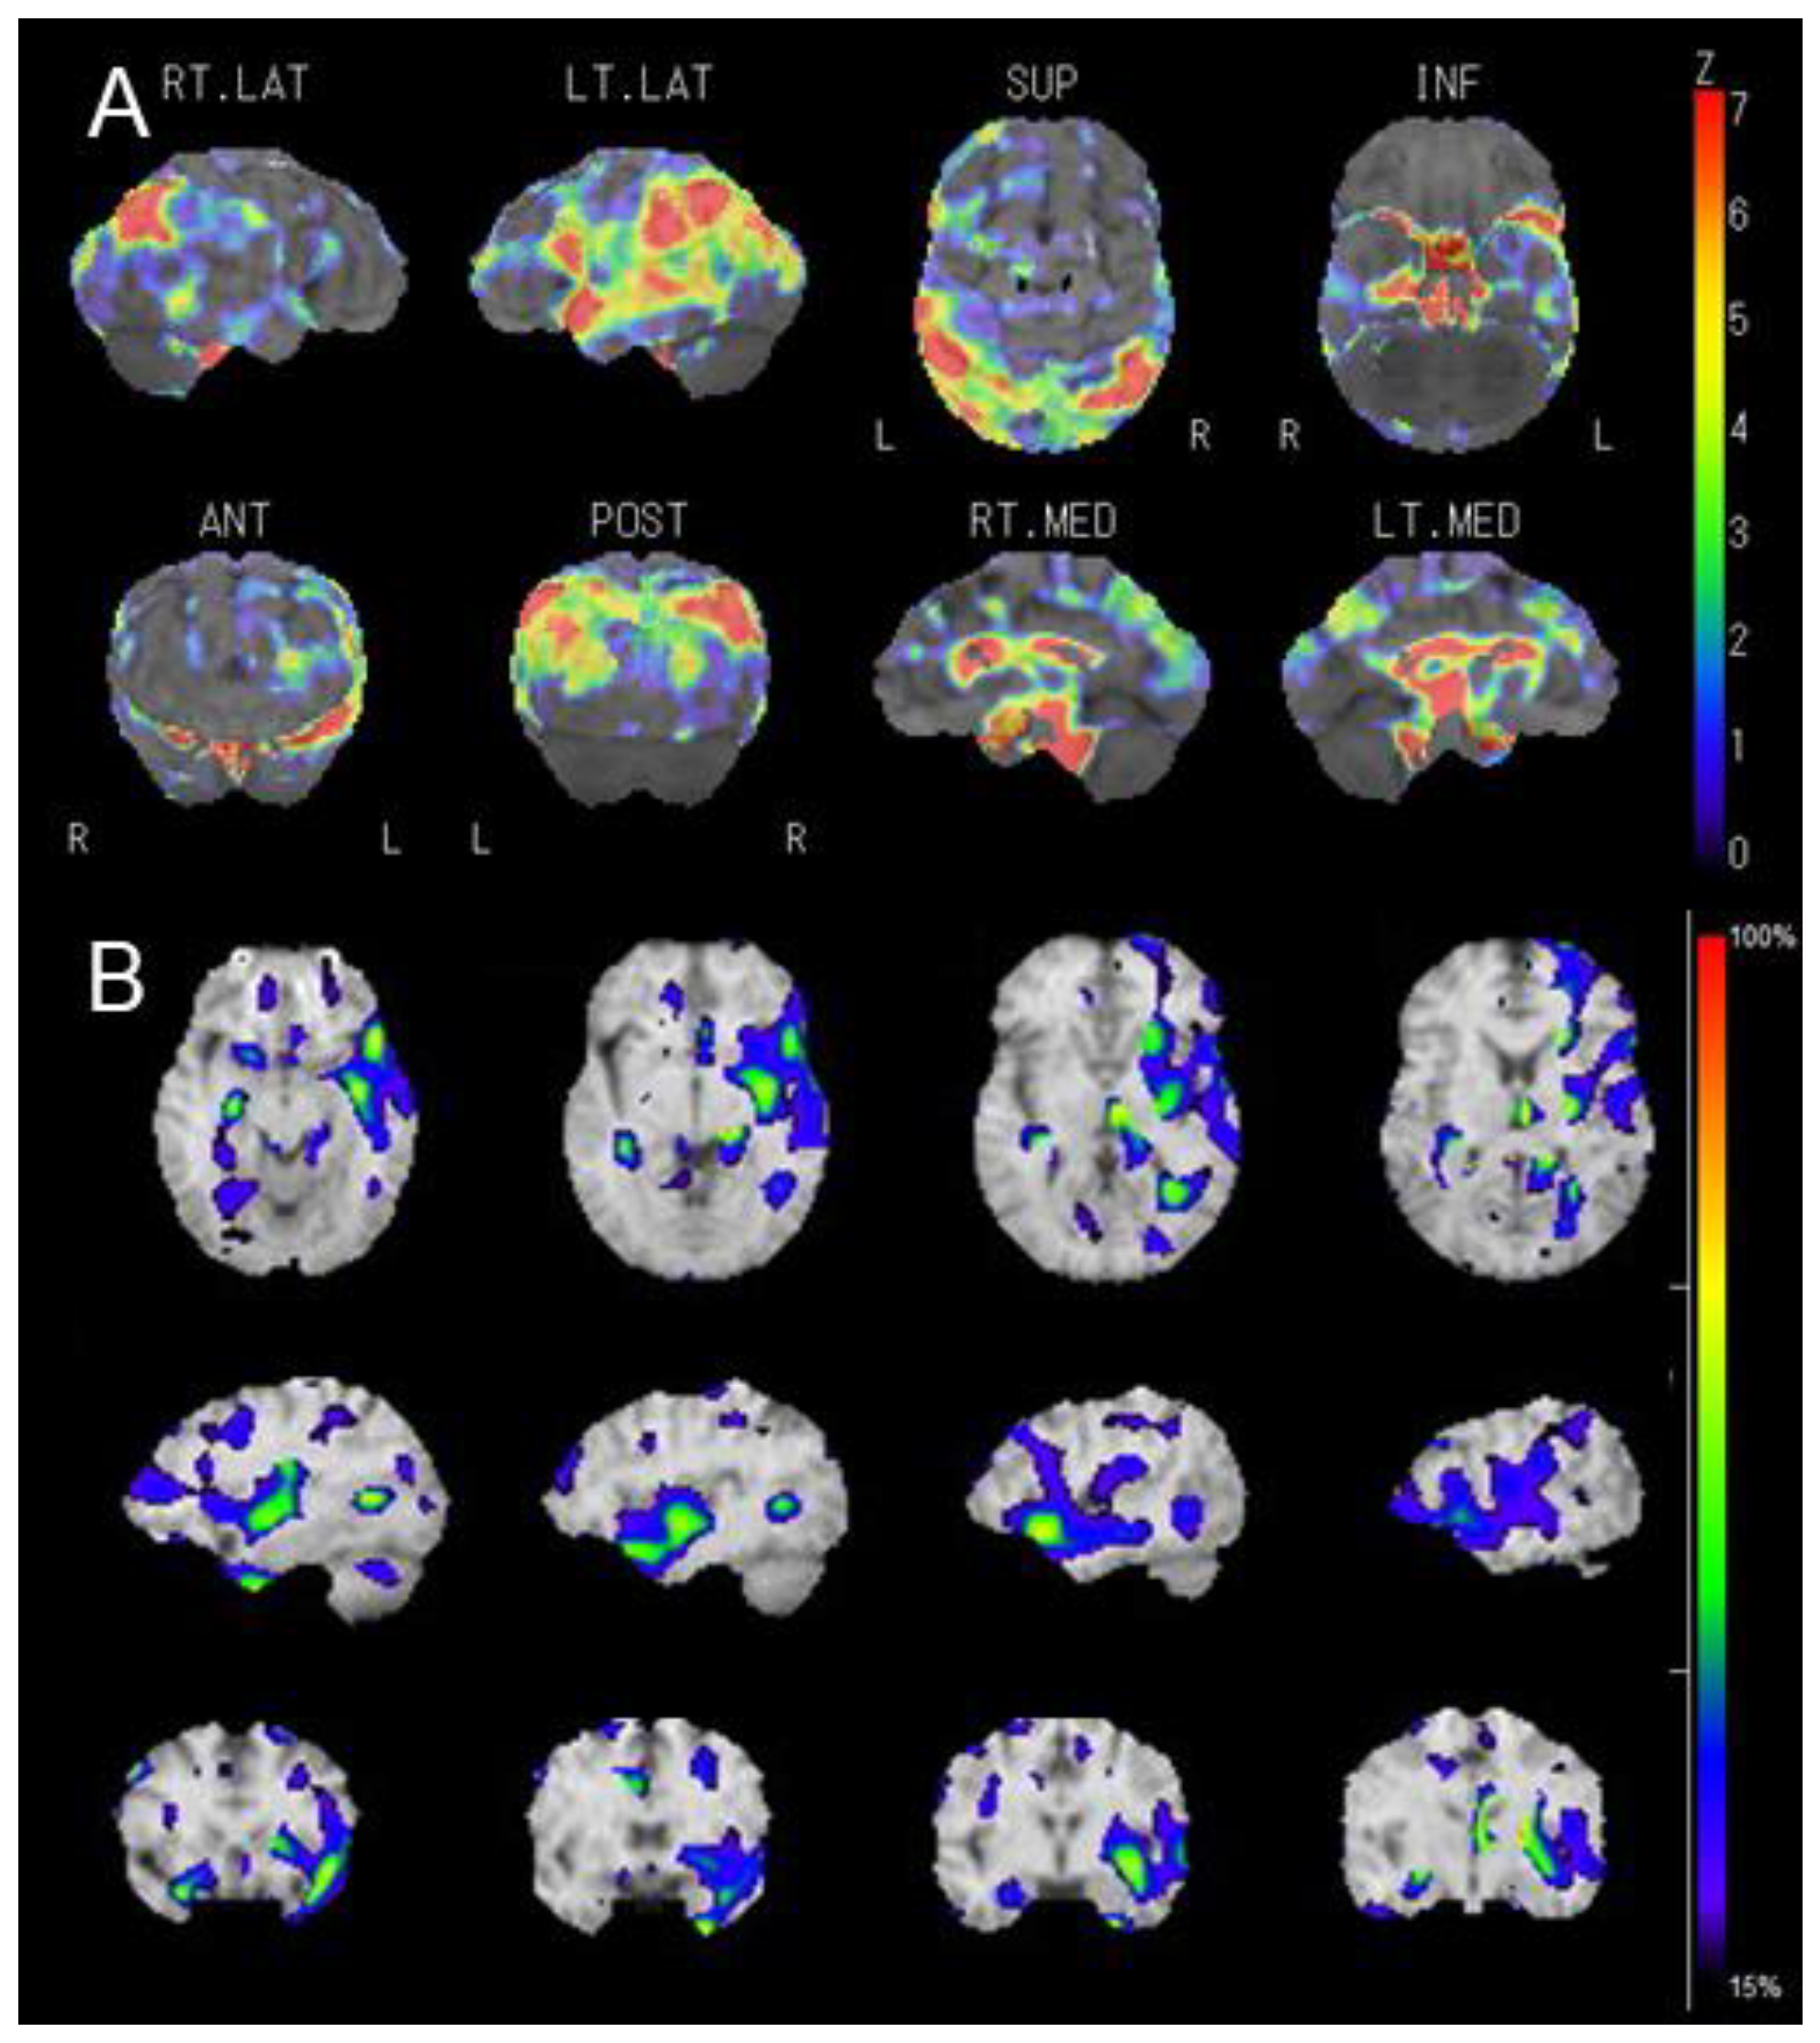

2. Case Presentation